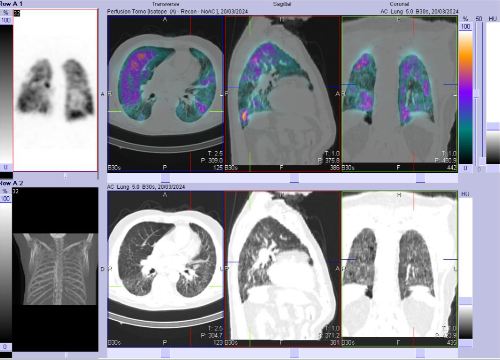

/ Obr. č. 1: Kombinovaná perfuzní a ventilační scintigrafie plic. Horní řada scintigramů – perfuze, dolní řada scintigramů – ventilace.

/ Obr. č. 2-7: SPECT/CT plic se zaměřením na vícečetné perfuzní defekty v obou plicních křídlech.

Na scintigramech pozorujeme vícečetné perfuzní defekty v obou plicích (v horním a dolním laloku pravé plíce a v horním a dolním laloku levé plíce). Dále je homogenní distribuce ventilace v obou plicích.

SPECT/CT potvrzuje tyto perfuzní defekty. Na ldCT je dále patrná Vámi popisovaná nespecifická intersticiální pneumonie, taktéž emfyzém, to však nevysvětluje diskrepanci mezi perfuzí a ventilací. Jde tedy o tzv. V/P mismatch.

Závěr: vícečetné perfuzní defekty v obou plicích (v horním a dolním laloku pravé plíce a v horním a dolním laloku levé plíce). Homogenní distribuce ventilace v obou plicích. V/P mismatch.

Relativní distribuce perfuze: L:P 40:60 %, relativní distribuce ventilace L:P 44:56 %.

Nález svědčí pro plicní embolizaci do obou plicních křídel.